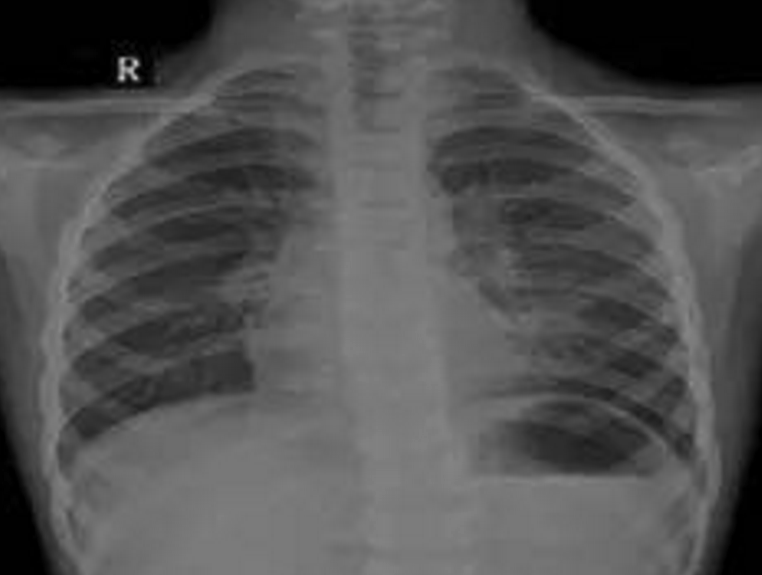

小文渊、小文博兄弟

2016年9月30日,39岁的徐士霞生下一对孪生宝宝孩子。然而孪生宝宝的降生只给这个家庭带来了三天短暂的欢乐。10月2日,小文渊、小文博相继出现抽搐、口吐白沫现象,齐齐哈尔第一医院诊断为先天性心脏病,并发肺炎、肺衰竭、呼吸衰竭,双双住进重症监护室。

5月11日下午,夫妻俩抱着文渊抵达上海儿童医学中心,经过检查,文渊重症肺炎、重度支气管炎,再不及时手术,会导致呼吸衰竭、心力衰竭。听着医生的诊断结果,夫妻俩泣不成声,家里的文博情况比哥哥还要严重,治疗费就像两座大山一样压在了夫妻俩肩上。